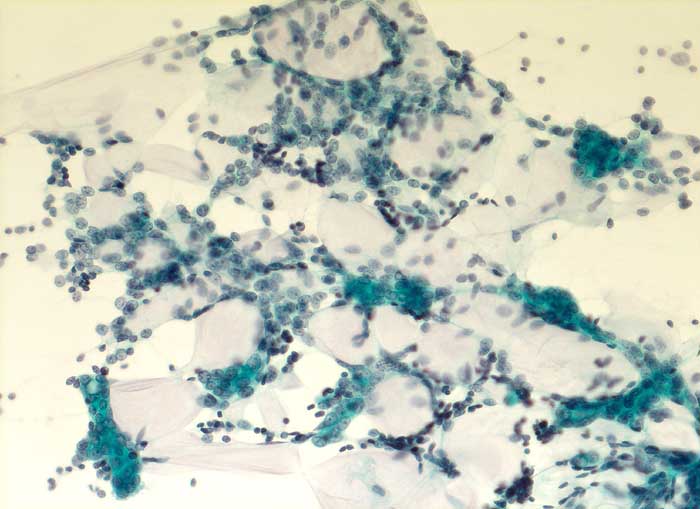

Adenoidzystisches Karzinom

Mamma

Feinnadelpunktion Mamma: Grosse, zum Teil dreidimensional erscheinende Verbände aus kleinen, ziemlich monomorphen Zellen. Die netzartig verzweigten Verbände umschliessen amorphe mukoide Matrix.

Zytologische Diagnose: Adenoidzystisches Karzinom.

Kommentar: Adenoidzystische Karzinome kommen vor allem im Bereich der Speicheldrüsen vor, treten aber auch in anderen Organen auf. Sie machen weniger als 0.1% - 0.2% der Mammakarzinome aus.